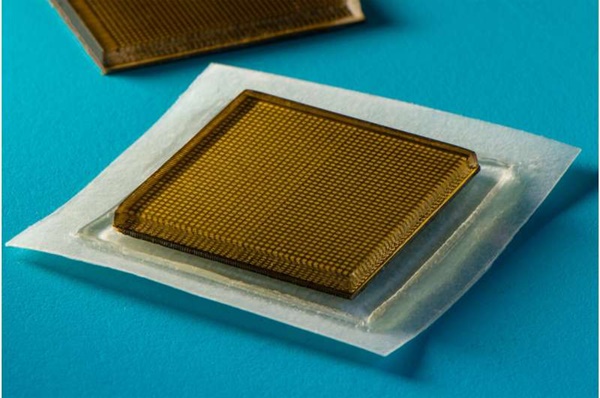

이 피부에 붙이는 패치는 놀랍다. 작은 우표 크기의 스티커를 보고 싶은 몸속 장기 피부 위에 붙이기만 하면 된다. 그러면 스티커에서 나온 초음파가 반사돼 환자의 심장, 폐, 그리고 다른 신체 깊은 곳에 있는 장기의 고해상도 이미지를 만들어 낸다.

MIT 팀의 새로운 초음파 스티커는 신축성 있는 접착층을 단단한 변환기 배열과 결합해 더 긴 시간 동안 고해상도 이미지를 생성한다. 왕 연구원은 “이러한 조합은 변환기의 상대적인 위치를 유지하면서 장치가 피부에 적합하도록 해 더 선명하고 정확한 이미지를 생성할 수 있게 해 준다”고 설명했다.

이 초음파 장치의 접착층은 주로 음파를 쉽게 전달하는 수성 물질인 고체 하이드로겔의 중간층을 감싸는 두 개의 얇은 탄소중합체(실리콘 고무같은 합성 고무) 층으로 만들어졌다. 기존의 초음파 젤과 달리 MIT 팀의 하이드로겔은 신축성을 갖는다.

MIT 포스트닥인 첸은 “탄성중합체는 하이드로겔의 탈수를 예방해 준다. 하이드로겔이 수분을 많이 공급받을 때에만 음파가 몸속 장기에 효과적으로 침투해 고해상도 영상을 제공할 수 있다”고 설명했다.

하단 탄소중합체 층은 피부에 달라붙도록 설계됐으며, 윗 층은 MIT 팀이 설계 제작한 견고한 변환기 배열에 부착된다. 전체 초음파 스티커의 크기는 작은 우표 정도인 약 2c㎡에 두께는 약 3mm다.